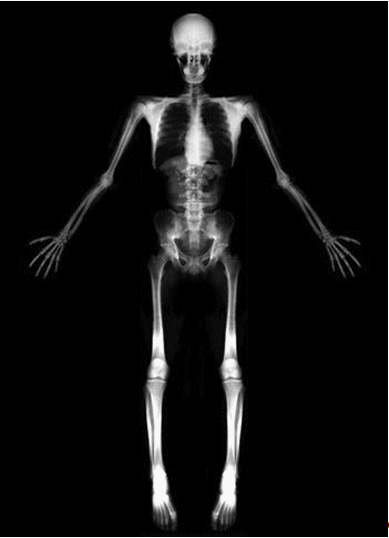

У человека более 200 костей (85 парных и 36 непарных), которые в зависимости от формы и функций делятся на:

В каждой кости содержатся все виды тканей, но преобладает костная, представляющая разновидность соединительной ткани. В состав кости входят органические

и неорганические вещества

. Неорганические вещества (65—70% сухой массы кости) — это в основном фосфор и кальций. Органические (30 — 35%) — это клетки кости, коллагеновые волокна.

Эластичность, упругость костей зависит от наличия в них органических веществ, а твердость обеспечивается минеральными солями. Кости детей более эластичны и упруги: в них преобладают органические вещества; кости же пожилых людей более хрупки: они содержат большое количество неорганических веществ.

На рост и формирование костей существенное влияние оказывают социально-экономические факторы: питание, окружающая среда и т.д. Дефицит питательных веществ, солей или нарушение обменных процессов, связанных с синтезом белка, незамедлительно отражаются на росте костей. Недостаток витаминов С, D, кальция или фосфора нарушает естественный процесс обызвествления и синтеза белка в костях, делает их более хрупкими. На изменение костей влияют и физические нагрузки. При систематическом выполнении значительных по объему и интенсивности статических и динамических упражнений кости становятся более массивными, в местах прикрепления мышц формируются хорошо выраженные утолщения — костные выступы, бугры и гребни. Происходит внутренняя перестройка компактного костного вещества, увеличиваются количество и размеры костных клеток, кости становятся значительно прочнее. Правильно организованная физическая нагрузка при выполнении силовых и скоростно-силовых упражнений способствует замедлению процесса старения костей.